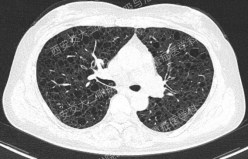

上图所示肺部囊性病变,双侧多发、大小不一,壁薄,形状不规则,呈圆形及扁平状为主,部分融合,分布多在纵隔胸膜下。入院后查血尿粪常规、肝肾功能电解质、凝血功能、血糖血脂心肌酶、BNP、肌钙蛋白正常;红细胞沉降率23mm/h,PCT、CRP正常;TB-spot阳性(阳性对照管反应水平123.49 pg/mL),TB-DNA、PPD试验、痰X-pert、痰涂片、痰培养均阴性;女性肿瘤标志物全套未见异常;结缔组织病相关指标:自身抗体ANA 1:100、CENP B阳性,CCP抗体25.1U/ml(正常参考值<17U/ml),ANCA、抗核抗体谱、体液免疫全套均阴性;血气分析大致正常,肺功能检查: FEV1占预计值78.2%,FEV1/FVC 69.55%,RV/TLC 49.62%,支气管舒张试验阴性,FeNO50 29.2ppb。

患者无吸烟史,二手烟接触不多。追问家族史,父母已故(具体不详),兄弟姐妹6人,大姐有肺大泡病史,未具体诊治,育有2子,均体健。进一步行双肾CT平扫提示双肾轻度积水,进一步行全外显子基因检测,回报FLCN突变:

该例患者BHD诊断明确,无皮肤及肾脏受累,仅表现为多发囊性肺病变。建议忌烟,避免受凉、劳累及剧烈运动,防范气胸。鉴于肺功异常,建议每年复查1次胸部CT及肺功能检查;每3年筛查1次肾脏MRI。同时建议其兄弟姐妹及其子完善症状前FLCN基因检测。